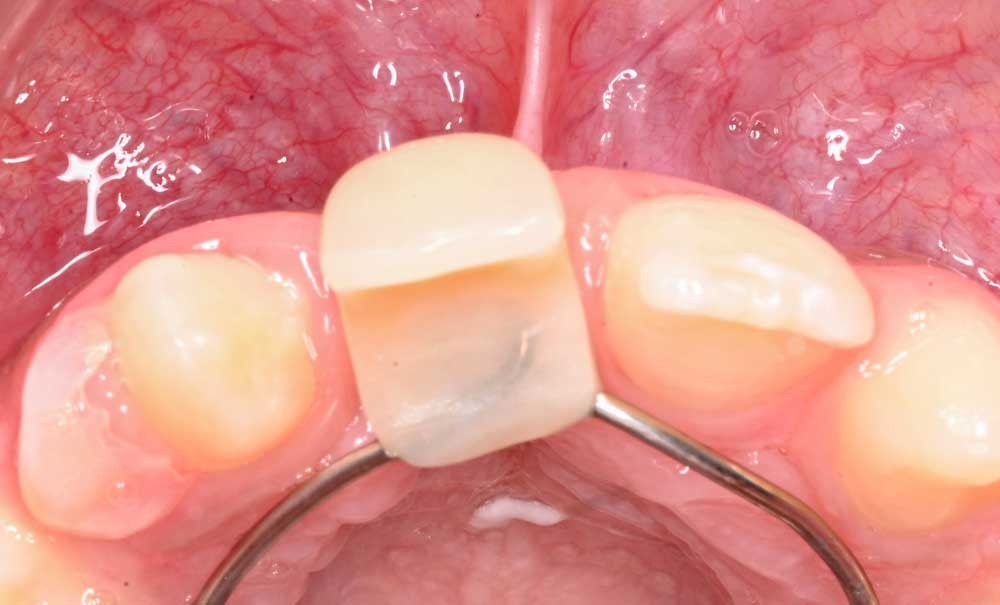

L’IADT recommande de réimplanter immédiatement une dent permanente expulsée sur le lieu du traumatisme (tableau 1). Si la réimplantation immédiate ne peut pas avoir lieu, il est recommandé de se rendre au cabinet dentaire le plus rapidement possible. La dent y sera réimplantée sans distinction du stade de développement radiculaire, du temps extra-alvéolaire ou du milieu de conservation dentaire (donc de l’état des cellules du ligament parodontal). Les milieux de conservation recommandés sont par ordre décroissant de préférence : lait > HBSS (Hanks’ Balanced Salt Solution) > salive > sérum physiologique > eau.